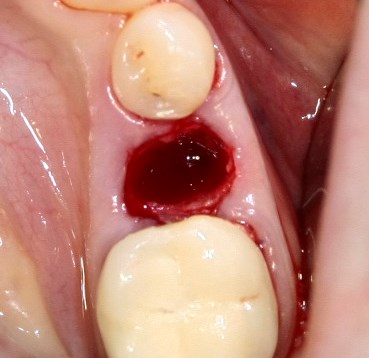

Немедленная имплантация — оптимальное решение в любой клинической ситуации